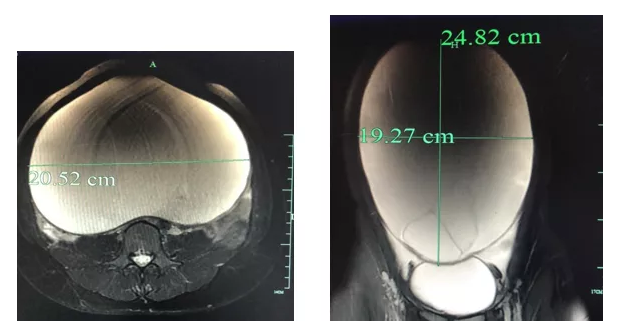

这一查,把小欣和许医生都吓了一大跳。只见小欣的肚子里有一个24*20*20cm的巨大包块,已经把她的整个腹腔都塞得满满当当,巨大的包块压迫到了周围的脏器,把脏器挤到了一边,整个盆腹腔基本上只能看到这个巨大的包块。

连从医经验丰富的许医生都感到吃惊,年纪轻轻,肚子里长了这么大的囊肿,这还是头一回遇见。